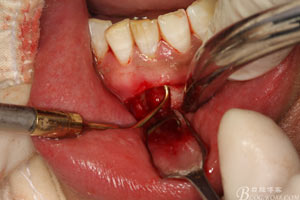

圖8.超聲骨刀去除根尖周?chē)腥竟琴|(zhì)